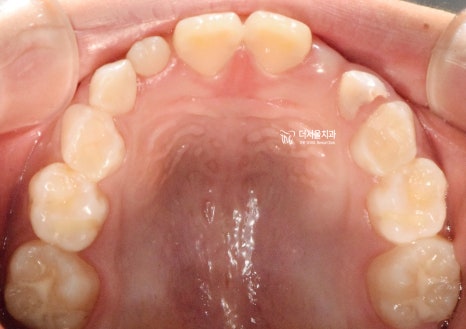

『구강 내 사진』

성장교정 이 필요한 이유는,

구강 내 사진에서도 뚜렷히 찾아볼 수 있습니다.

유치가 빠지면서 영구치아가 올라오고 있는

혼합치열기에서, 영구치가 올라올 수 있는

충분한 공간을 확보하면서

턱의 위치를 바로 잡는것이 핵심포인트입니다.

우선 여기서 봐야 될 큰 문제는

1) 절단교합(Edge to edge bite) 입니다.

윗니가 아랫니를 물고 있어야 되는데,

서로 절단연끼리 맞닿고 있죠.